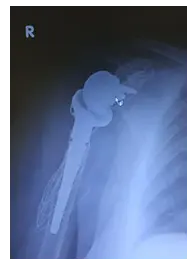

Başka bir merkezde humerus üst uç kırığı ameliyatı olmuş ve kaynama sağlanamamış hastanın protez öncesi grafisi ve sağ ve sol omuz hareket farkı.

Protez konulduktan sonraki grafisi.